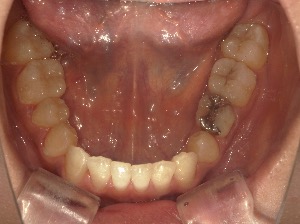

患者さんの年齢 20代 女性 症状 ガタガタを治したい 治療内容 マウスピース矯正治療 費用 90万(税抜) 治療期間・回数 治療期間2年、通院回数10回 メリット 笑顔が綺麗 デメリット・リスク 期間がかかることがある - マウスピース矯正

before